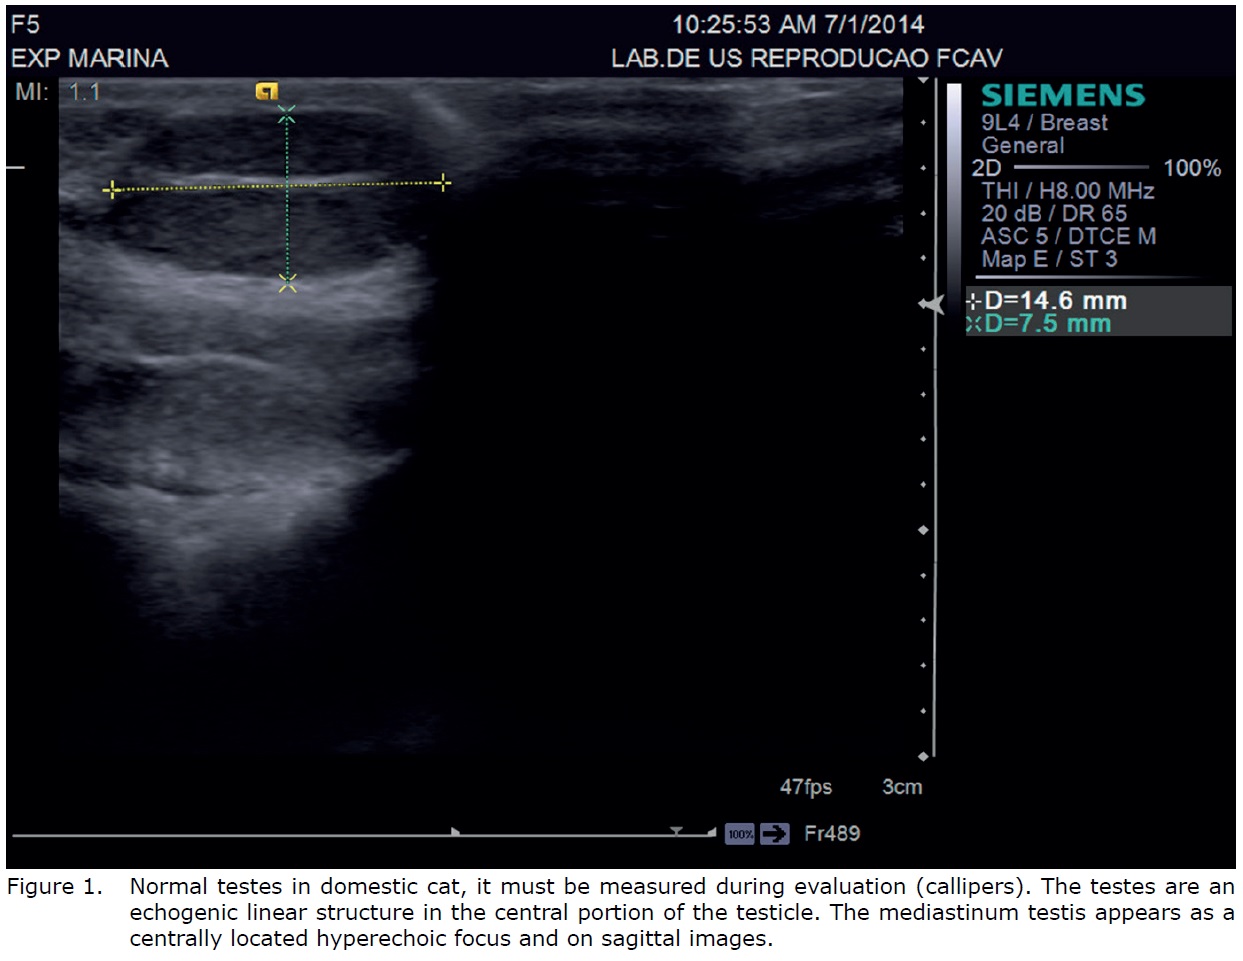

Normal testicles are of medium echogenicity and have a fine, homogeneous echotexture (12). The testicular border is characterized by a thin, smooth and hyperechoic tunica albuginea (Figure 1). On transverse images, the mediastinum testis appears as a centrally located hyperechoic focus and on sagittal images, a central hyperechoic line is visible that represents the mediastinum testis (11).

B-mode ultrasonography. Ultrasonographic study of the testes is a common diagnostic imaging procedure. It has performed after clipping of the scrotum region (10). Some examiners recommend use of a standoff pad and ultrasound gel is preferred as a contact medium over alcohol because of the risk of scrotal irritation (11).

The testicles should be examined with a high frequency transducer (at least 7.5MHz) (5,6,7,8,9,10,11). A 5MHz or lower transducer may not provide sufficient resolution to detect small lesions or subtle parenchymal changes (5). In addition, a linear transducer with broad contact area and good resolution in the near field is preferable over a sector or curvilinear transducer. The testicles should be scanned in transverse, longitudinal, and dorsal planes (1,5,11).

The B-mode ultrasonography in testicular animals allows the determination of biometric values such as volume and size, assessment of topographic and parenchymal features, position and its internal constitution (4). In cats, the testes are readily located within the scrotum and they have easily located by ultrasound (1).